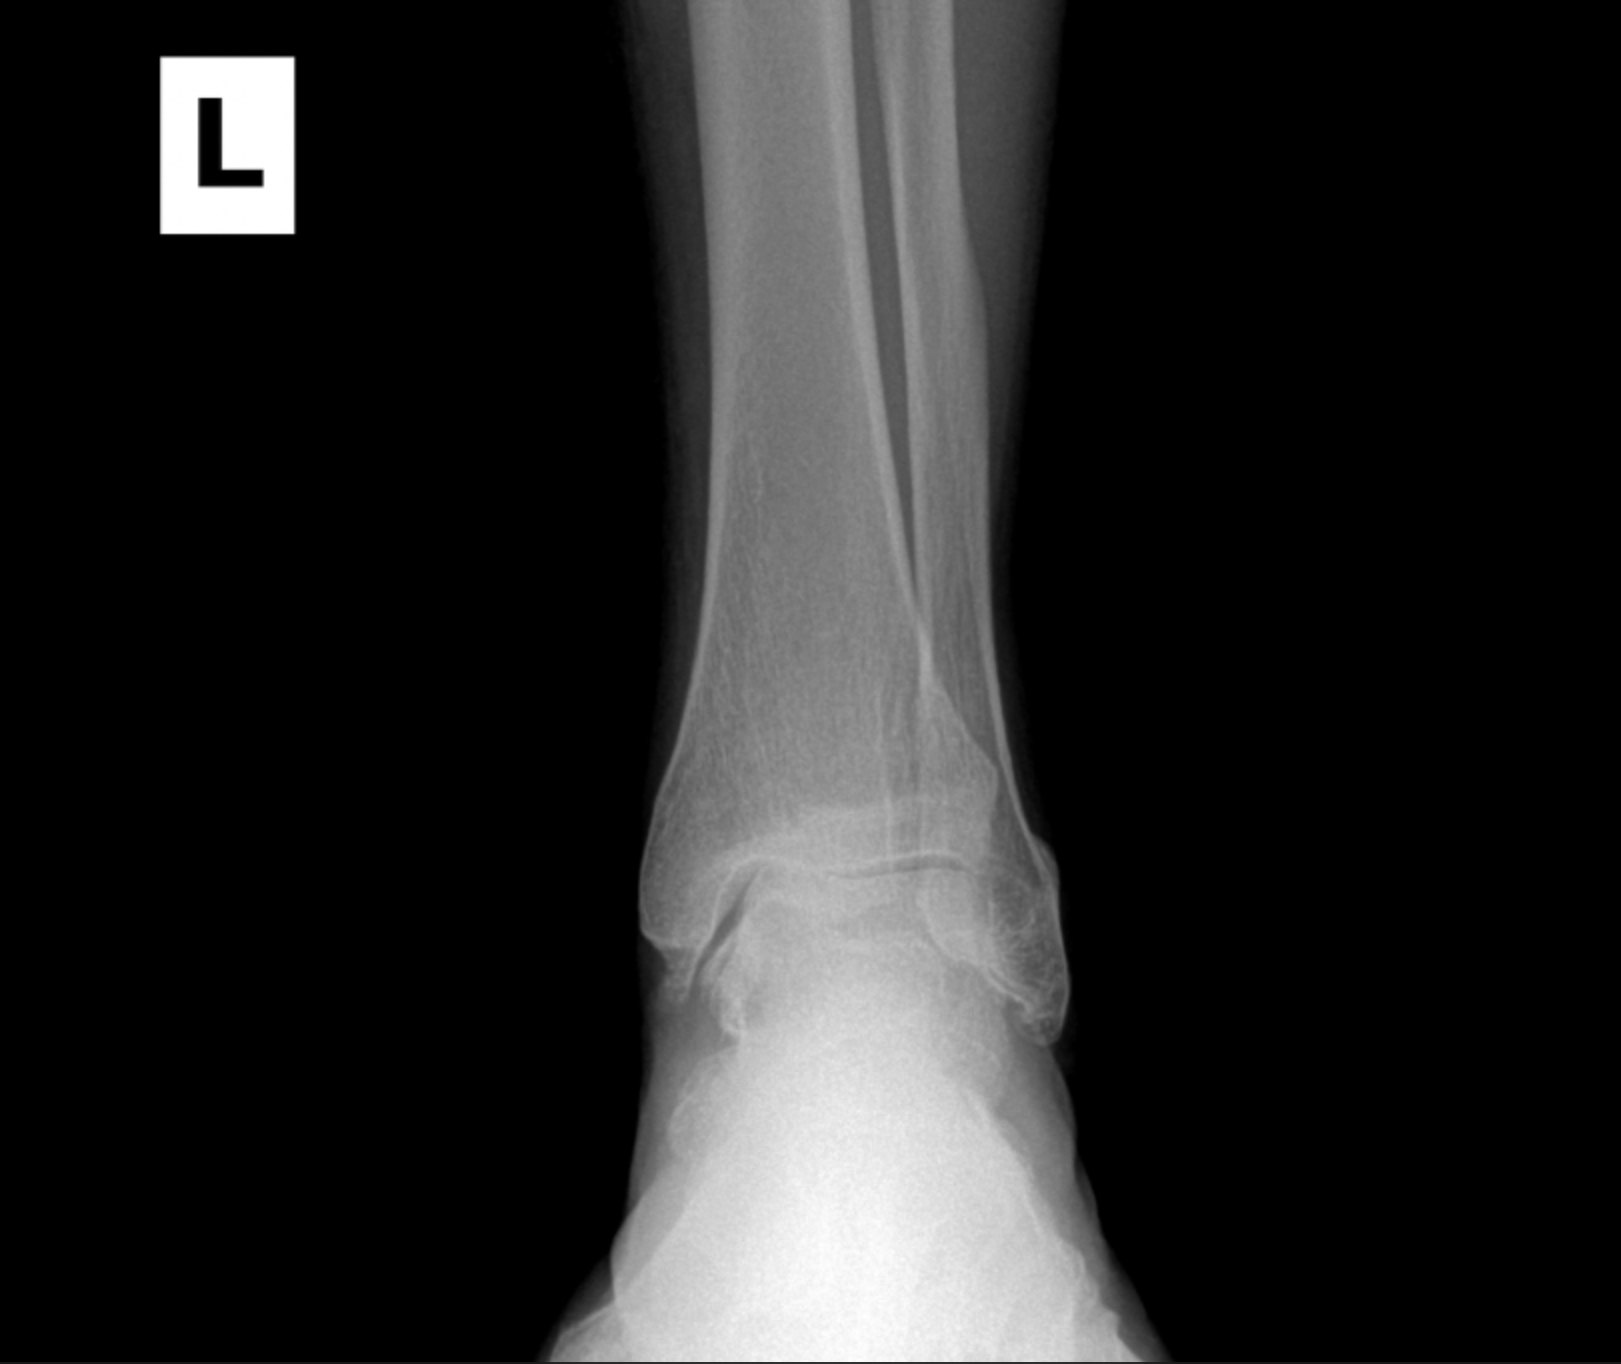

Foot & Ankle Replacement

Coming Soon